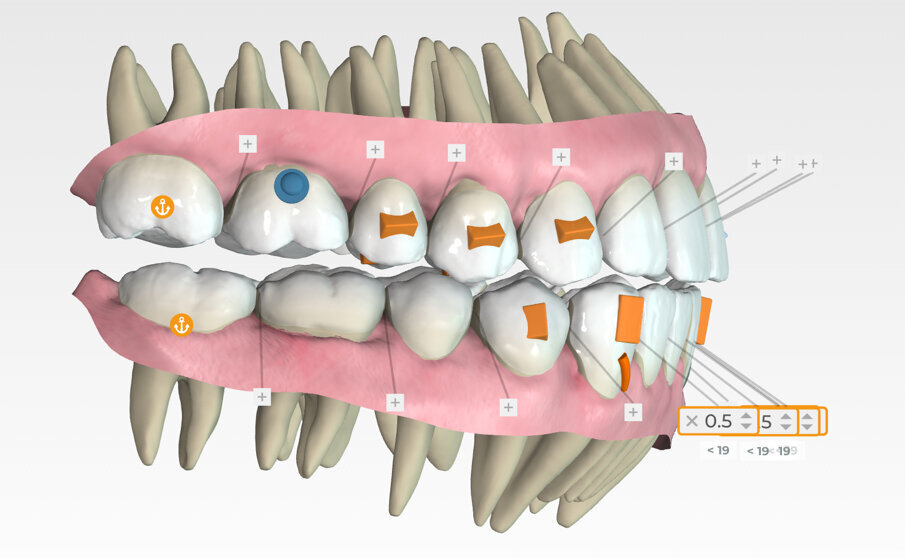

Specifically, the plan prescribed upper arch expansion and bilateral molar and second premolar intrusion of 3 mm. To support intrusion and prevent reciprocal lifting of the aligners, 4 mm wide occlusally beveled retentive attachments were designed and placed on the premolars. (Fig. 11)

Button cut-outs were prescribed on the upper first molars, and elastic hooks on the lower canines to attach 5/16, 4.5-ounce Class III inter-arch elastics. (Fig. 12)